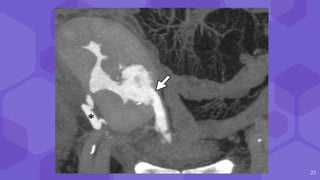

26

27

• #28 Coronal contrast-enhanced delayed phase MIP CT image shows focal urinary contrast material leak from the collecting system (arrow) Note the contrast material–filled transplant ureter (*)

• #27 delayed static images show ill-defined radiopharmaceutical accumulation anterior and lateral to the transplant kidney, compatible with a urinoma, which was confirmed at surgery Fluid aspirated from a urinoma will have creatinine and potassium concentrations greater than blood serum, whereas lymphocele aspirate will creatinine and potassium concentrations same has serologic concentrations

• #26  (a) US image shows a nonspecific perinephric fluid collection (arrows). (b)99mTc MAG3 renal scintigram shows prompt radiopharmaceutical uptake in the allograft (*) and subsequent excretion into the urinary bladder (arrowhead).

• #25 A urinoma is a fluid collection that has leaked from the renal collecting system usually found in the first 10 days after transplantation, most commonly interposed between the allograft and the urinary bladder Urinomas usually occur inadequate blood supply to the ureter or elevated pressures from obstruction The US appearance of urinoma may overlap with that of lymphocele or seroma, appearing as a simple hypoechoic fluid collection. Further diagnostic workup may include delayed contrast-enhanced CT or MRI to assess the collecting system and ureteral anastomoses and detect leakage of excreted contrast material Retrograde urography or renal scintigraphy can also be performed.

24 Urinoma ⬢ Fluid collectionfrom renal collecting system ⬢ 10 days after transplant ⬢ Inadequate blood supply to ureter ⬢ Usg appearance overlap --lymphocele /seroma